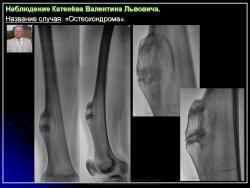

Остеохондрома (костно-хрящевой экзостоз).

Наблюдение Катенёва В.Л.

Приложения:

1.201607190013.jpg2.201607190017.jpg3.201607190018.jpg4.201607190016.jpg5.201607190019.jpg6.201607190020.jpg7.201607190021.jpg